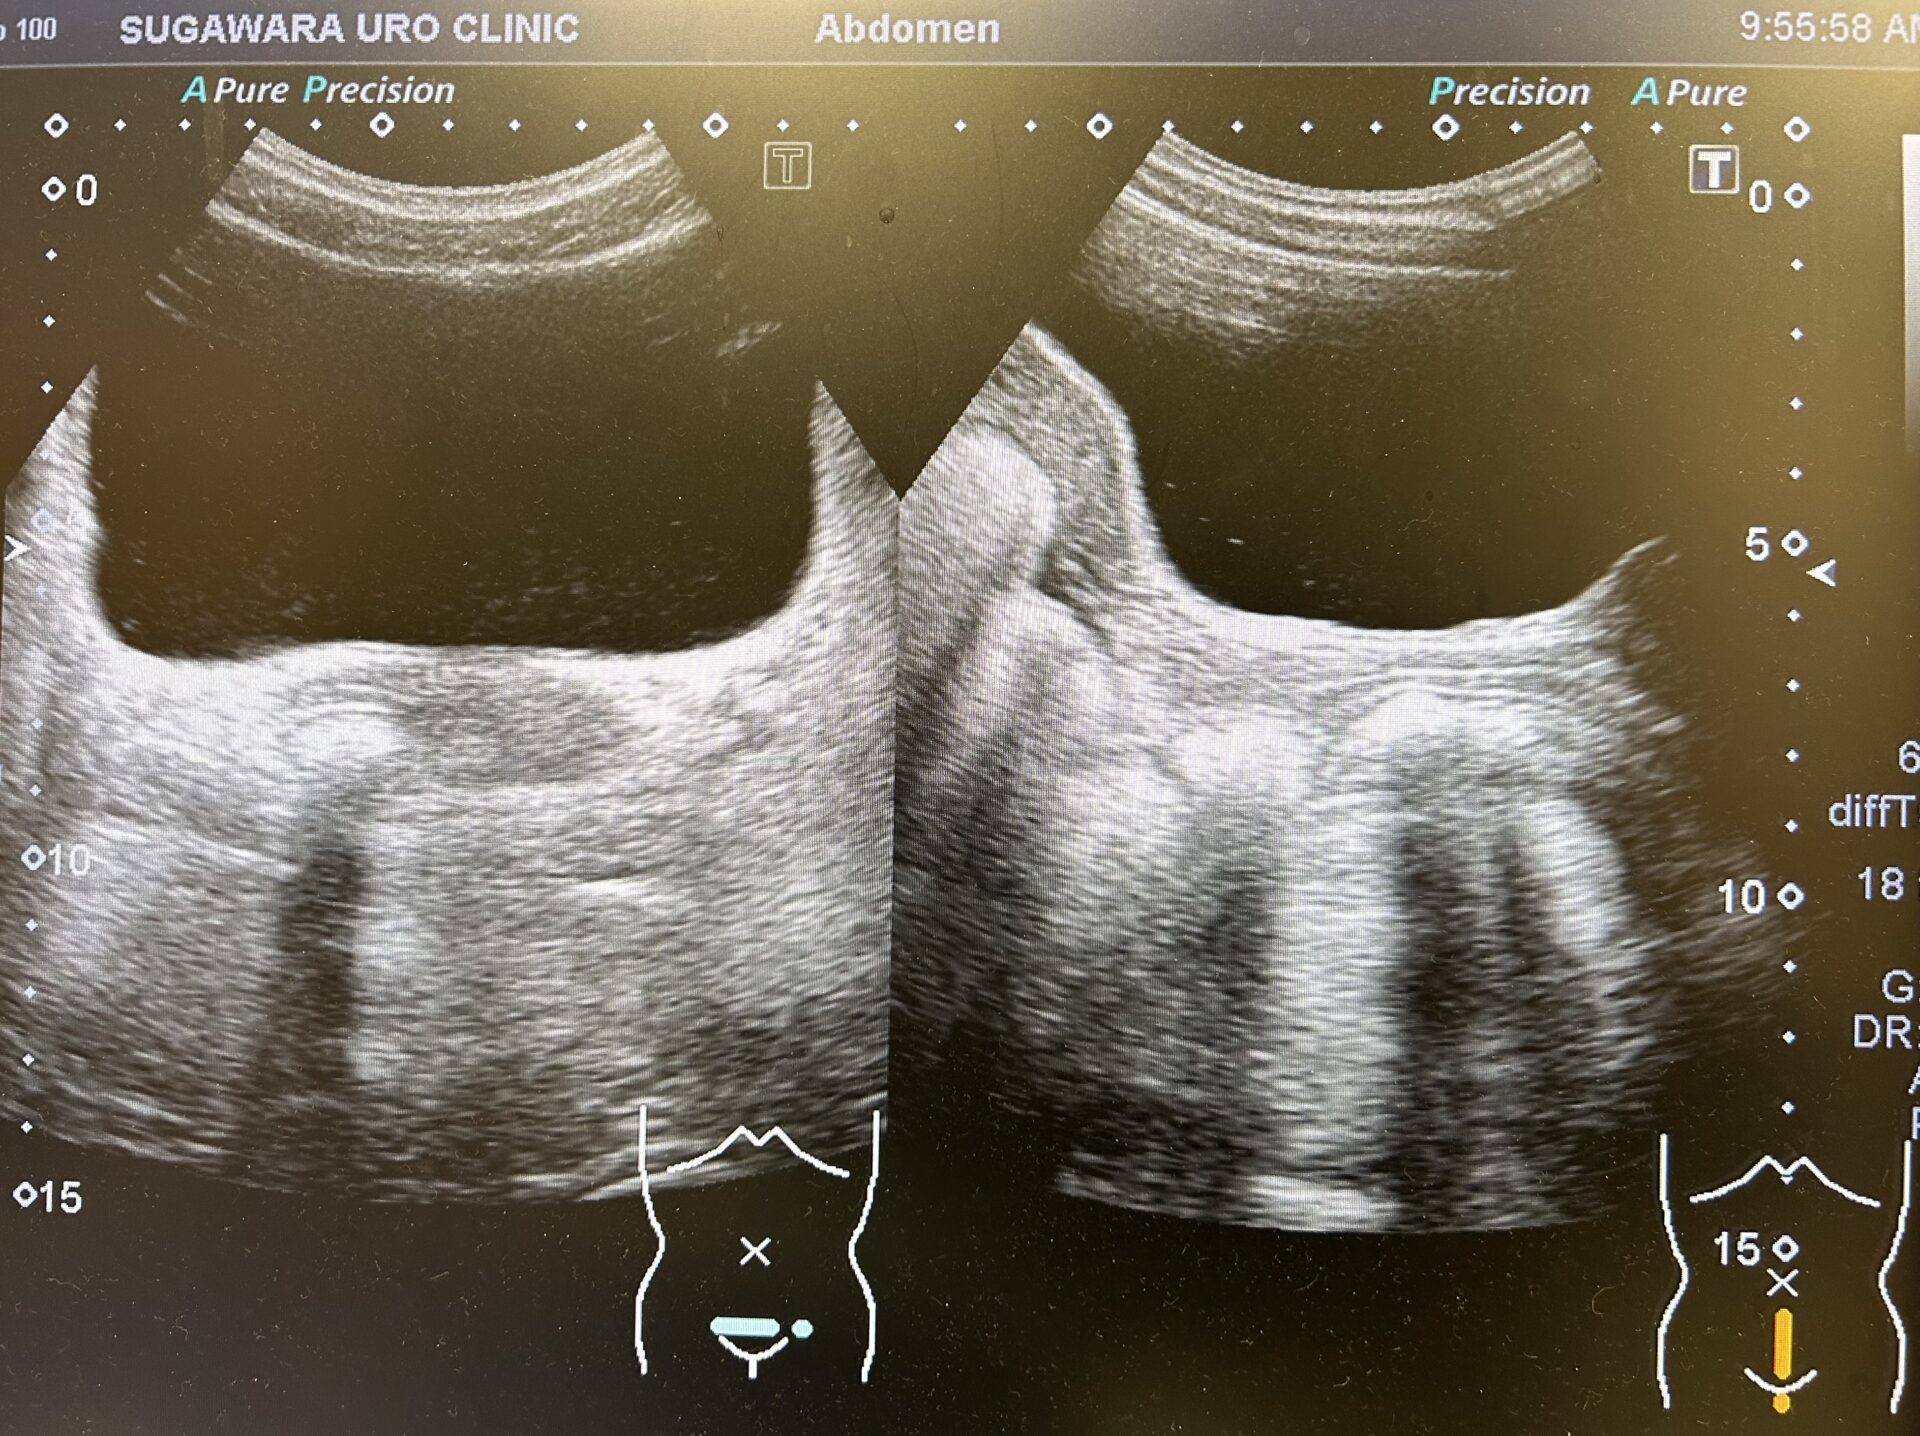

尿路エコー上左腎水腎症(-)、右腎水腎症(-)、膀胱内SOL(-)も尿の貯留を認めておりました。

【超音波像:膀胱内に尿が貯留しています。膀胱内には器質的な要因は認められませんでした】